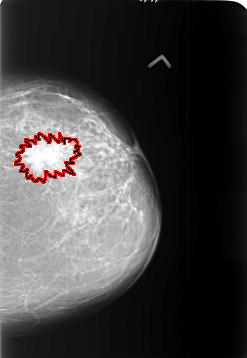

B_3401_1.LEFT_CC

LEFT_CC LINES 5728 PIXELS_PER_LINE 3944 BITS_PER_PIXEL 12 RESOLUTION 50 OVERLAY

FILE: B_3401_1.LEFT_CC.OVERLAY

TOTAL_ABNORMALITIES 1

ABNORMALITY 1

LESION_TYPE MASS SHAPE IRREGULAR-ARCHITECTURAL_DISTORTION MARGINS SPICULATED

ASSESSMENT 5

SUBTLETY 5

PATHOLOGY MALIGNANT

TOTAL_OUTLINES 2

BOUNDARY